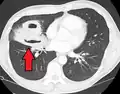

Pulmonary abscess on CT scan -